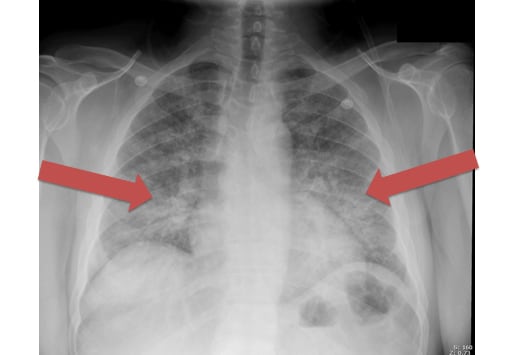

Asbestosis imaging medscape reference. Oct 19, 2015 asbestosis. Posteroanterior chest radiograph reveals a few reticulonodular opacities at the lung bases consistent with mild asbestosis. Asbestosis medscape. Etiology. The incidence of asbestosis varies with the cumulative dose of inhaled fibers; the greater the cumulative dose, the higher the incidence of asbestosis. Radiology articles medscape reference. Radiology articles covering imaging, techniques, findings, symptoms, diagnosis, staging, treatment, prognosis, and followup. Peer reviewed and uptodate. Asbestos lung cancer lungcancerclaims. Billions set aside for asbestos lung cancer victims. Act now. Benign asbestos pleural diseases medscape. Benign asbestos pleural diseases. Stephen j. Chapman, bmbch, mrcp, william o.C. Cookson, md, dphil, frcp, frs, a. William musk, md, fracp, y.C. Gary lee, Asbestosis directory find news, features, and pictures. Find webmd's comprehensive coverage of asbestosis including medical reference, news, pictures, videos, and more. Mesothelioma lawsuit? Over $3.1 billion paid out. Learn more about the latest in. Rhabdomyolysis causes, symptoms and treatment. Rhabdomyolysis symptoms and causes what are the symptoms of rhabdomyolysis? The muscle damage causes inflammation leading to tenderness, swelling, and.